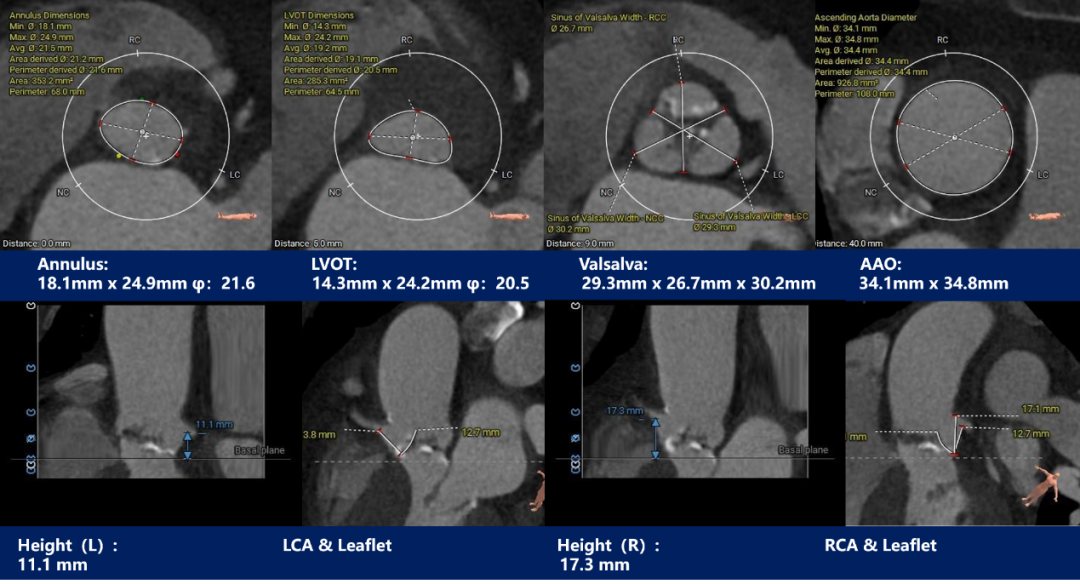

主动脉根部测量

CT特点:中重度钙化三叶式主动脉瓣,瓣叶明显增生肥厚。左右冠开口高度可,无冗长瓣叶;非横位心,心室肌肥厚。

3. 依据瓣环及瓣上测量结果,采用20mm球囊预扩张,预装AV23瓣膜;